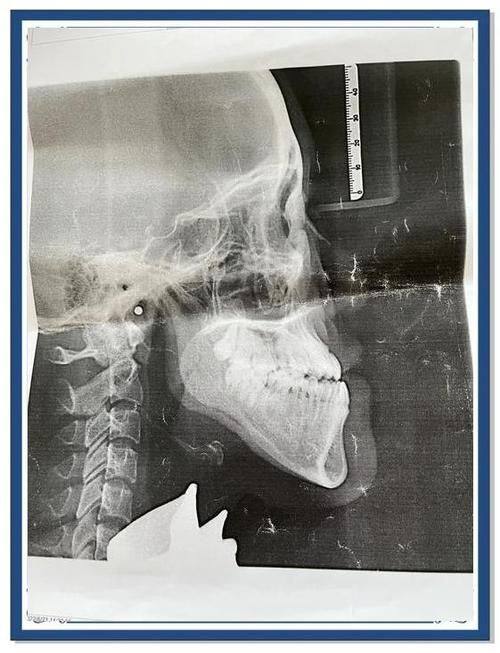

1. 凸嘴矫正:凸嘴不仅影响面部美观,还可能影响口腔功能。尹泰镐院长在凸嘴矫正方面有着丰富的经验。他会根据患者的具体情况,制定个性化的矫正方案。对于一些轻度凸嘴患者,可能采用牙齿矫正的方式,通过调整牙齿的排列来改善凸嘴情况;而对于较为重度的凸嘴患者,则可能结合外科手术进行矫正。他的矫正技术能够有效改善面部轮廓,让患者拥有更加美观的面容。

2. 地包天矫正:地包天会导致面部不协调,影响患者的自信心。尹泰镐院长能够正确判断地包天的成因和类型,采用合适的矫正方法。对于牙性地包天,他可以通过牙齿矫正来调整牙齿的咬合关系;对于骨性地包天,则可能需要进行手术治疗。他的矫正方案能够较大程度地修复患者正常的咬合功能和面部形态。